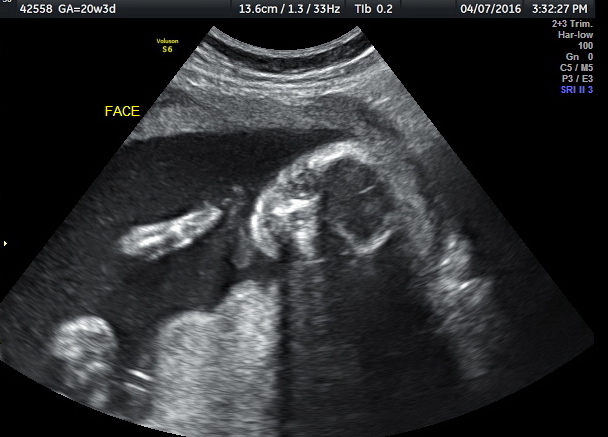

After the OB exam, I was sent to Maternal Fetal Medicine for an ultrasound to assess the baby’s size and viability. The MFM told me baby looked beautiful for a 26-weeker, but was very honest about what a rocky road we’d have ahead if we were to deliver now. Survival rate is about 90%, but beyond sheer survivability, we face potential heart, lung, eye and brain complications. He said the magnesium would help protect the brain and that they’d give me a steroid shot that would strengthen the lungs — just in case. The good news was that there was still a fair amount of fluid around the baby, so even if I were leaking amniotic fluid (we were still waiting on test results), it was likely a slow leak. And he said in rare cases, a pinhole leak could even repair itself. Either way, he didn’t think I was in immediate danger of “draining the pool,” so to speak, but if I were to completely rupture, I’d deliver within 48 hours.